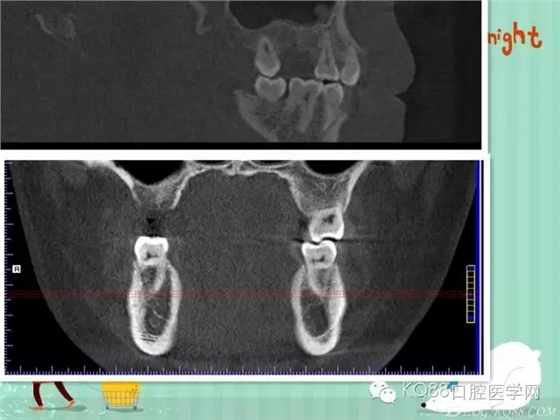

下面兩張是種植前后的對(duì)比片子。

手術(shù)前

手術(shù)后。